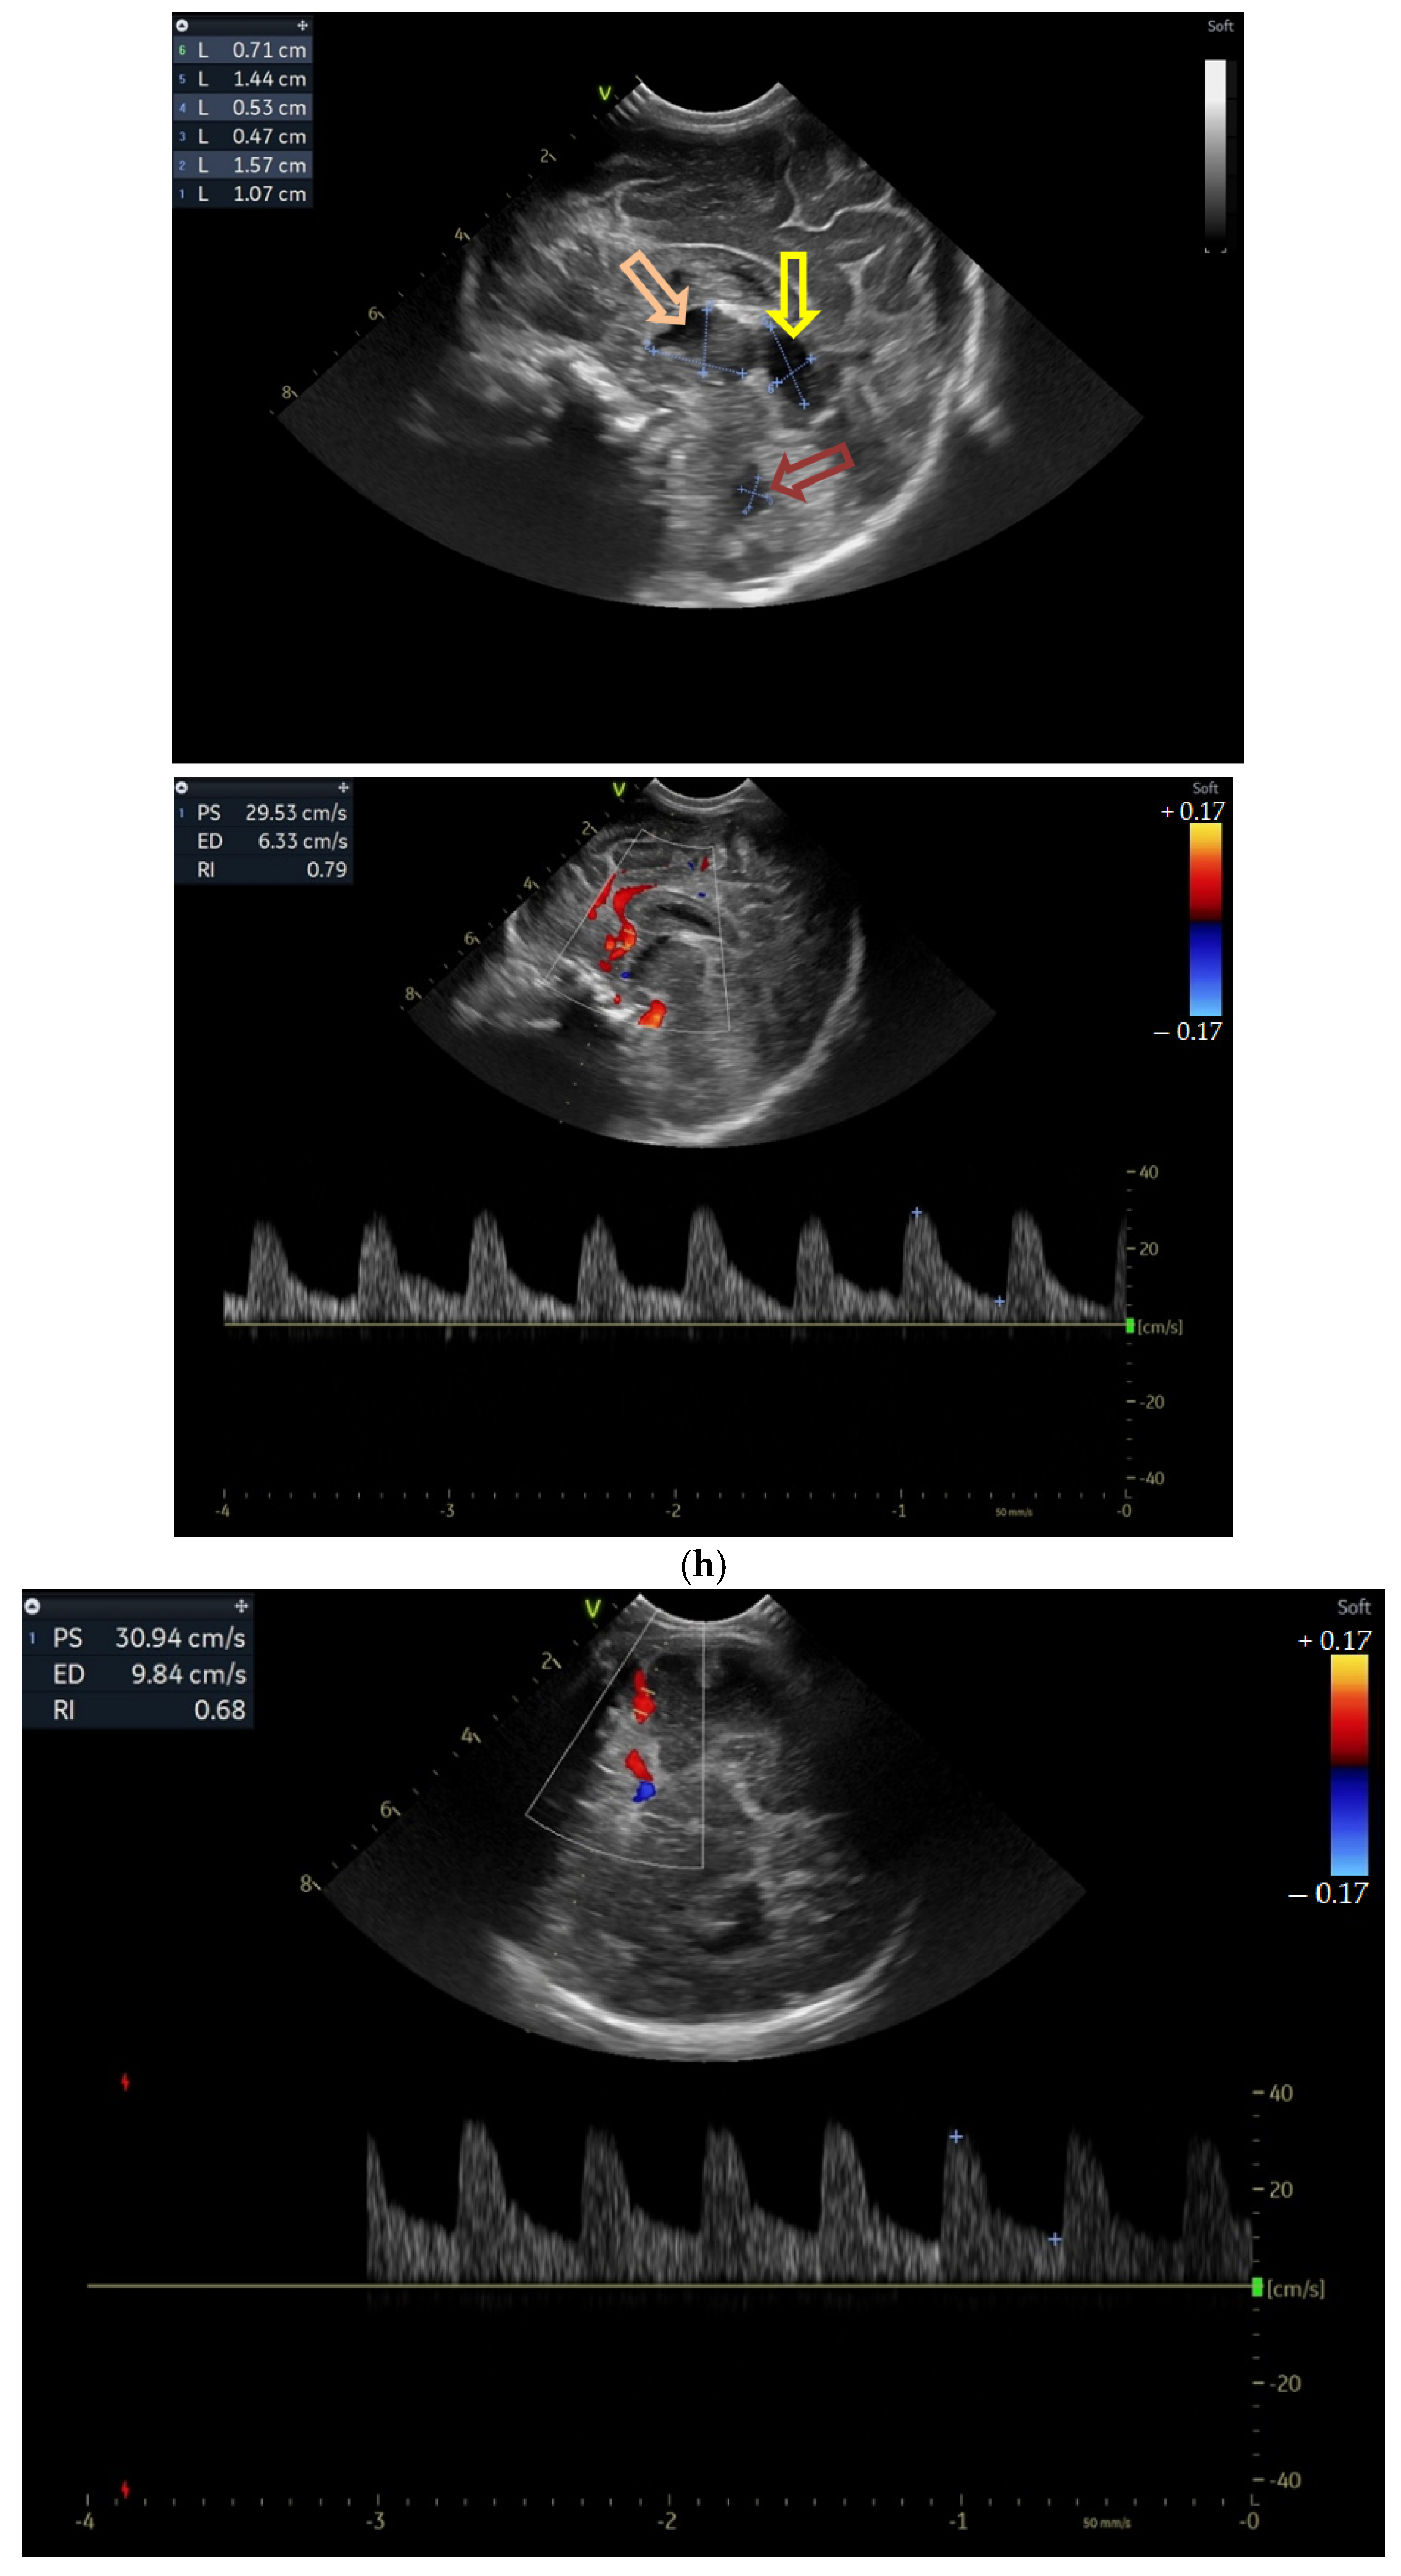

(a) Cranial ultrasound. Day one. Coronal view. D1 and D2—Levine index measurement. D3—cisterna magna measurement (personal image collection). (b) Cranial ultrasound. Day one. Coronal view. Lateral ventricle dilatation. LV—lateral ventricles. PC—plexus choroidus (personal image collection). (c) Cranial ultrasound. Day one. Right lateral ventricle. D1—thalamo-occipital distance measurement. Yellow arrow—parieto-occipital hyperechoic images (personal image collection). (d) Cranial ultrasound. Day one. Left lateral ventricle. D1—thalamo-occipital distance measurement. Yellow arrow—parieto-occipital hyperechoic images (personal image collection). (e) Day three. Cranial ultrasound. Coronal view. Ventricular asymmetry. D1 and D2—Levine index measurement. D3 and D4—anterior horn width measurement. Left ventricular enlargement (personal image collection). (f) Day three. Cranial ultrasound. Coronal view. Ventricular asymmetry (left ventricle larger than right ventricle). Yellow arrows—periventricular hyperechoic images are becoming more visible (personal image collection). (g) Day three. Cranial ultrasound. Coronal view. Linear probe. Ventricular asymmetry (left ventricle larger than right ventricle). LV—lateral ventricle (anterior horns). IHF—interhemispheric fissure. Yellow arrows—hyperechoic images in the thalamic-caudate groove (suggestive of a germinal matrix hemorrhage) (personal image collection). (h,i) Day 13. First LP. Cranial ultrasound. Coronal view. Up (before LP). D1 and D2—Levine index measurement. LV—lateral ventricles (anterior horns). IHF—interhemispheric fissure. Down (after LP). Dimensions of ventricles were reduced after LP. D1 and D2—anterior horn width. LV—lateral ventricles (anterior horns). OH—occipital horn (personal image collection). (j,k) Day 19. Second LP. Cranial ultrasound. Coronal view. Dimensions of ventricles were reduced after LP. Left (before LP). D1 and D2—Levine index measurement. Right (after LP). D1 and D2—Levine index measurement (personal image collection). (l) Day 39. Cranial ultrasound. Coronal view. Yellow arrows—periventricular cystic hyperechoic images—suggesting periventricular leukomalacia (cystic form) (personal image collection). (m) Head circumference-for-age. “X” symbols represent the measurements performed from birth and follow-up examinations. Initially, the head circumference was under the curve (personal image collection) [28].

During the in-stay, two lumbar punctures (LP) were performed (Figure 1h–k).

(a) Cranial ultrasound. Coronal view. Enlargement of the lateral ventricles with hyperechoic and third ventricle dilation. D1, D2—Levine index measurement. D3, D4—anterior horn width measurement. D5—third ventricle (personal image collection). (b) Cranial ultrasound. Sagittal view. Up—left ventricle. D1, D2—lateral ventricle measurements and thalamo-occipital horn width. Down—right ventricle. D1, D2—lateral ventricle measurements and thalamo-occipital horn width (personal image collection). (c) Cranial ultrasound. Sagittal view. Up—enlargement of the third and fourth ventricles. Measurements of the ventricles. Down—measurement of the resistive index (RI) performed on the anterior cerebral artery (ACA) using Doppler flow measurements. RI—0.74 (personal image collection). (d) Cranial ultrasound. Transtemporal view. Yellow arrow—enlargement of the Sylvian aqueduct (personal image collection). (e) Cranial ultrasound. Sagittal view. Yellow arrow—arachnoid cyst posterior to the third ventricle (personal image collection). (f) Cranial ultrasound. Coronal view. Lateral ventricles and third ventricle enlargement. D1, D2—Levine index measurement. D3, D6—right lateral ventricle measurement (anterior horn width). D4, D5—left lateral ventricle measurement (anterior horn width) (personal image collection). (g) Cranial ultrasound. Sagittal view. Left—left ventricle. D1—thalamo-occipital distance measurement. Right—right ventricle. D2—thalamo-occipital distance measurement (personal image collection). (h) Cranial ultrasound. Coronal view. Up—orange arrow—third ventricle. Red arrow—fourth ventricles. Yellow arrow—arachnoid cyst. Down—resistive index measured on the anterior cerebral artery. RI—0.79 (personal image collection). (i) Cranial ultrasound. Transversal view. Up—RI precompression value on the middle cerebral artery performed with Doppler examination. RI—68. Down—RI post-compression value on the middle cerebral artery performed with Doppler examination. RI—0.79 (personal image collection). (j) Cranial ultrasound. Up—coronal view. L1, L2—Levine index measurement of the lateral ventricles. Down—sagittal view. L1, L2—measurement of the thalamo-occipital distance (personal image collection). (k) Cranial ultrasound. Sagittal view. L1, L2—measurement of the third ventricle. L3, L4—measurement of the fourth ventricle. L5, L6—measurement of the arachnoid cyst (personal image collection). (l). Head circumference-for-age. “X” symbols represent the measurements performed from birth and follow-up examinations. Head circumference was still under the curve during follow-up examinations (personal image collection) [28].

The CUS examination performed at 48 h after birth showed increases in the diameters of all ventricles. The resistive index presented an increase as well. The bregmatic fontanelle started bulging. The dimensions of the Sylvian aqueduct were not modified (Figure 3f–h).

The CUS examinations performed at four days and seven days after birth showed stabilization regarding the values of the diameters. The pre- and post-compression values of the resistive index of the middle cerebral artery showed a delta-RI of 0.11 (pre—0.68, post—0.79, Figure 3i).